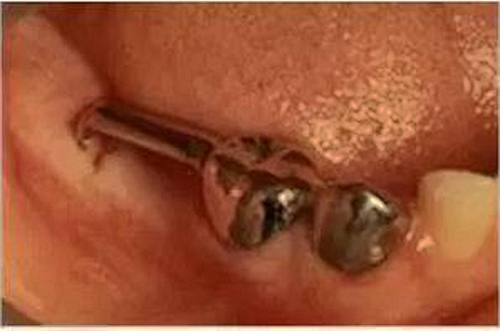

④遠(yuǎn)中導(dǎo)板式間隙保持器

乳牙缺失致恒牙“亂長”,這個(gè)“間隙保持器”可預(yù)防

這種間隙保持器是將導(dǎo)板插入牙齦中,主要用于孩子的六齡牙(最先長出的第一顆恒磨牙)還沒有萌出,但是這個(gè)牙前面的乳牙缺失的情況。

因?yàn)樽詈蠓降难例X缺失,沒有可以用來固定帶環(huán)絲圈的牙齒,因此需要一個(gè)金屬導(dǎo)板插入到牙齦中,防止間隙關(guān)閉。

這種保持器需要經(jīng)常檢查并作出調(diào)整,防止阻擋下方恒牙的萌出。為了減少這種裝置的使用,牙醫(yī)經(jīng)常會(huì)盡可能保留乳牙,直到牙齦下方的恒牙已經(jīng)發(fā)育到可以萌出。